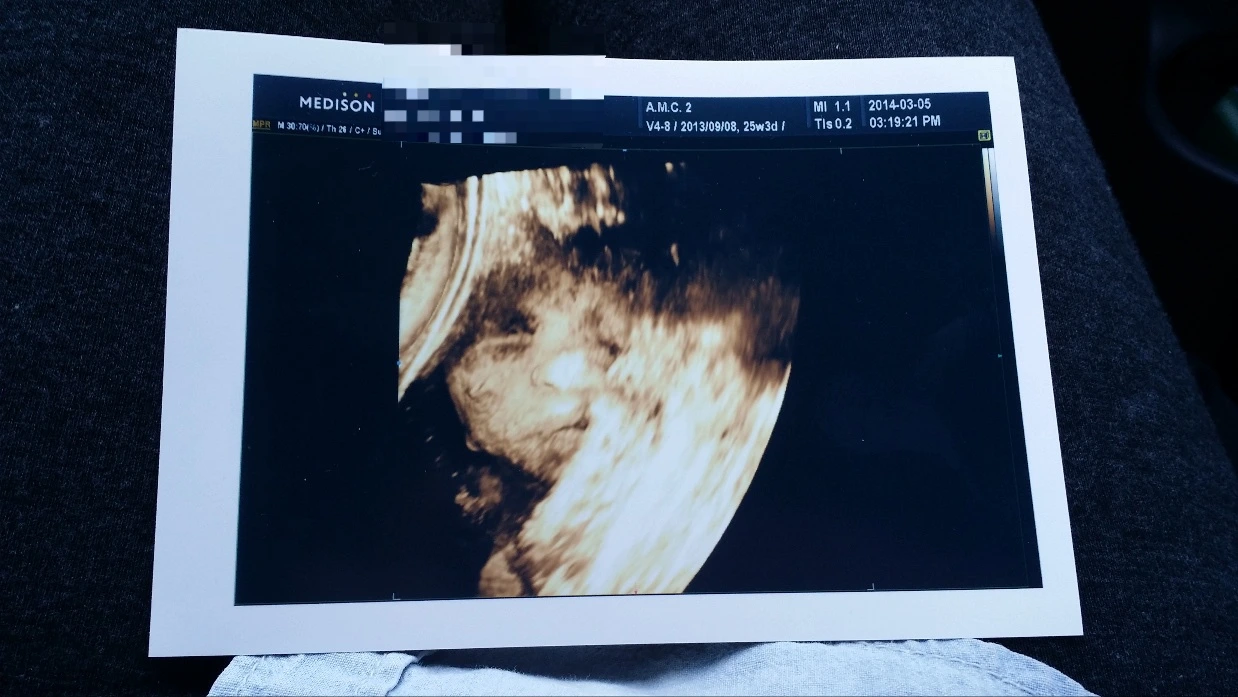

입체초음파를 보는 날이었다 누굴 닮았을까 궁금하기도 하고 초음파 볼 때 달달한 음료를 먹고 가면 뱃속태아도 잘 움직인다는 말을 듣고 편의점에서 초콜릿우유를 한잔 마시고 병원으로 들어갔다 사실 달달한 음료가 마시고 싶기도 했다 임신하면 뭐든 다 잘 먹게 된답니다

다시 배드에 누워 초음파를 보는데 드디어 선생님이 간신히 초음파 장비로 가을이의 얼굴을 보여주었다 근데 자궁벽에 붙어 얼굴 반쪽만 살짝 보여주었다

내 눈에는 반쪽 얼굴이지만 그것도 너무 이쁜 것이 아닌가 역시 이제 나도 고슴도치 엄마가 되어가는구나 생각이 들었다